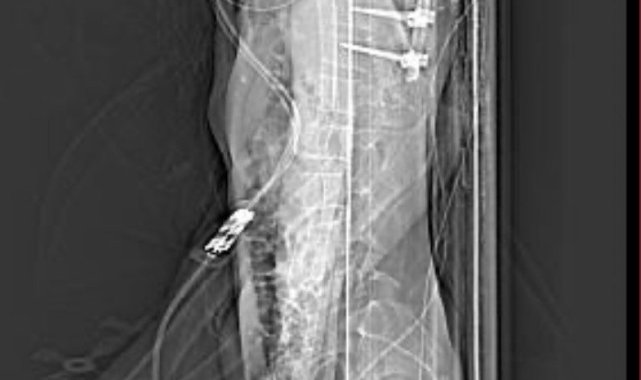

Eskişehir'de ara sokaktan çıkan otomobile çarparak ağır yaralanan 20 yaşındaki motosiklet sürücüsünün babası, oğlunun sağlık durumunun iyiye gittiğini söylerken, motosiklet kullanıcılarına da ekipman tavsiyesinde bulundu.25 Eylül günü Gündoğdu Mahallesi Cumhuriyet Bulvarı'nda yaşanan kazada, Şenel Sokak'tan bulvara çıkan Birol T. idaresindeki 34 HBF 007 otomobile, 20 yaşındaki Yusuf Gündoğmuş idaresindeki 26 AIZ 906 plakalı motosiklet yandan çarpmıştı. Kazada iki sürücü de yaralanırken, 20 yaşındaki motosiklet sürücüsünün sağlık durumu ağır olduğu öğrenilmişti. Kazadan sonra Eskişehir Şehir Hastanesi'nde uzun bir süre yoğun bakımda yatan ve birden fazla ameliyat geçiren Gündoğmuş, adeta ölümden döndü. Yoğun bakım tedavisi sırasında genç motosiklet sürücüsünün ailesinin sürekli dua ettiği öğrenildi.Oğlu ölümden dönen baba doktorlara teşekkür ettiGeçirdiği operasyonlar sayesinde kritik dönemi yavaş yavaş atlatan ve bilinci açılan Yusuf Gündoğmuş'un tedavisine sevk edildiği Eskişehir Osmangazi Üniversitesi Tıp Fakültesi Hastanesi'nde devam ediliyor. Genç motosiklet sürücüsünün 45 yaşındaki babası Hidayet Gündoğmuş, oğlunun iyileşmesi sebebiyle önce Allah'a sonra emeği geçen doktorlara minnettar olduğunu dile getirdi. Hem Eskişehir Şehir Hastanesi'nde hem de Eskişehir Osmangazi Üniversitesi Tıp Fakültesi Hastanesi'nde doktorların oğluna iyi baktığını söyleyen baba Gündoğmuş, oldukça mutlu olduğunu dile getirdi. Oğlu gibi kendisinin de motosiklete tutkun olduğunu söyleyen Hidayet Gündoğmuş, kaza görüntülerini izlediğinde ekipmanın ne kadar önemli olduğunu bir kez daha anladığına dikkat çekti. Biri kız olmak üzere üç çocuk babası Gündoğmuş, kendi gibi motosiklet tutkunu olan çocuklarına ekipman kullanmayı ısrarla söylediğini ve Yusuf Gündoğmuş'un da ekipmanları sayesinde hayatta kaldığını ifade etti"Rabbim kimseye yaşatmasın"Konuyla alakalı konuşan Hidayet Gündoğmuş, "Şükürler olsun, her gün daha iyiye gidiyoruz, daha iyiyiz. Şehir hastanesiyle ameliyatlarımız bitti. Oradaki doktorlarımıza çok teşekkür ederim, çok ilgilendiler. Tıp fakültesindeki plastik cerrahide estetik ameliyatlarımız var. Allah'a şükür her gün daha iyiye gidiyoruz. Çocuğumuz ayağa kalktı, sağlığı yerinde. Kaza anını gördüğümde anlatamam; kendim Diyarbakır'daydım, uzun yoldaydım. Rabbim kimseye yaşatmasın. Kötü bir duygu; çok şey demek isterim. Ben kendim de motor kullanıyorum. Bizde aile boyu hepimizde motor var. Kendim 18 yaşından beri kullanırım. Şükürler olsun bugüne kadar bir kazam olmadı. Çocuklarıma istedikleri motoru aldım. Amcalarında da var, amcasının çocuklarında da var. Bizim Eskişehir'imizin halkı motora karşı biraz daha duyarsız. Motor kullanan arkadaşlarımız, kardeşlerimiz de cahil. Arabaların sağından soldan trafikte çok geçerim, "geçivereyim" gibisinden hareketler var. Biz halk olarak yaya iken trafikteki taşıtlara kızarız, arabadayken yayalara kızarız. Halk olarak çok bencil bir toplumuz. Eğitim desem eğitim değil, kültür desem kültür değil. Herkes kendi çıkarları veya bencil davranışları yüzünden trafikte birçok kaza görüyoruz. Her gün kazalar oluyor. Motora binen özellikle gençlerimizi ve kuryelerimizi acele etmemeleri konusunda uyarıyorum" diye konuştu."Bedeli biraz ağır oldu ama şükürler olsun Rabbime"Trafikte sıklıkla seyreden kuryeler başta olmak üzere motosiklet kullanıcılarını uyaran Gündoğmuş, şöyle devam etti;"Özellikle kuryeler, insanların siparişlerini iki dakika önce götüreceğim diye kendi hayatlarını, kendi canlarını riske atmasınlar; sevdiklerini üzmesinler. Biz böyle ağır bir kaza yaşadık; keşke yaşamasaydık. Bedeli biraz ağır oldu ama şükürler olsun Rabbime. Daha iyiyiz. Her gün daha iyiye gidiyoruz. Herkes dikkatli olsun. Yani motora binenler de araçlara karşı dikkat etsinler. Araç kullanan vatandaşlarımızın da motorları görmelerini istiyorum.""Evladımız gayet iyi, sağlıklı, yerinde"Oğlunun tedavi sürecini anlatan Hidayet Gündoğmuş, şunları kaydetti:"Beş gün entübe edildi. Ne olacağı belli değildi çıkmama ihtimali vardı. Şükürler olsun doktorlarımız ve Rabbim sayesinde entübeden çıktık. Hatta ciğerin birisinde infilak vardı; ciğer sorunumuzdan dolayı özellikle yoğun bakımda entübediydik. Beş günün sonunda ciğerleri toparlamaya başladı; entübeden çıkarttılar. Solunumu normale döndü. Sırayla sağlığı yerine gelmeye başladı. Bir hafta sonra kolundan ameliyat oldu platin koydular. Omurilikten ameliyat olduk. Omuriliğinde ilk röntgende tek kırık gördüler; üç kemiği birbirine bağlayacaklardı. Sonradan ikinci röntgende üç kırık olduğunu gördük; yedi kemiği birbirine bağladılar. Omuriliğe platin takıldı. 14 tane civatamız var. Şükürler olsun doktorlarımıza, Allah razı olsun. Evladımız gayet iyi, sağlıklı, yerinde. Artık işte suratta, çenede, burunda, elmacık kemiklerinde parçalı kırıklarımız var. Osman Gazi Fakültesi'nde Allah'ın izniyle buradaki hocalarımıza, önce Rabbim'e sonra hocalarımıza emanet çocuğumuz. İnşallah daha iyi olacağız; ben kendi adıma söylüyorum. Çocuğuma, her motora bindiklerinde sürekli kask ve montlarını giymelerini tembihliyordum. Giymediklerinde fırça atıyordum. Eskişehir'de birçok yerde tanınırız, tanırlar. Sevenimiz, eşimiz, dostumuz çok; uyarırlar, telefon gelir, haber verirler. Her duyduğumda, gördüğümde söylerim. Sağ olsun, çocuğum da o gün beni dinlemiş, kaskını takmış. Şükürler olsun ki takmış; takmasaydı o gün, o kazada belki çocuğumuzu kaybederdik."